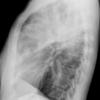

different case

Round pneumonia

Date: 11/28/2009

Views: 5860